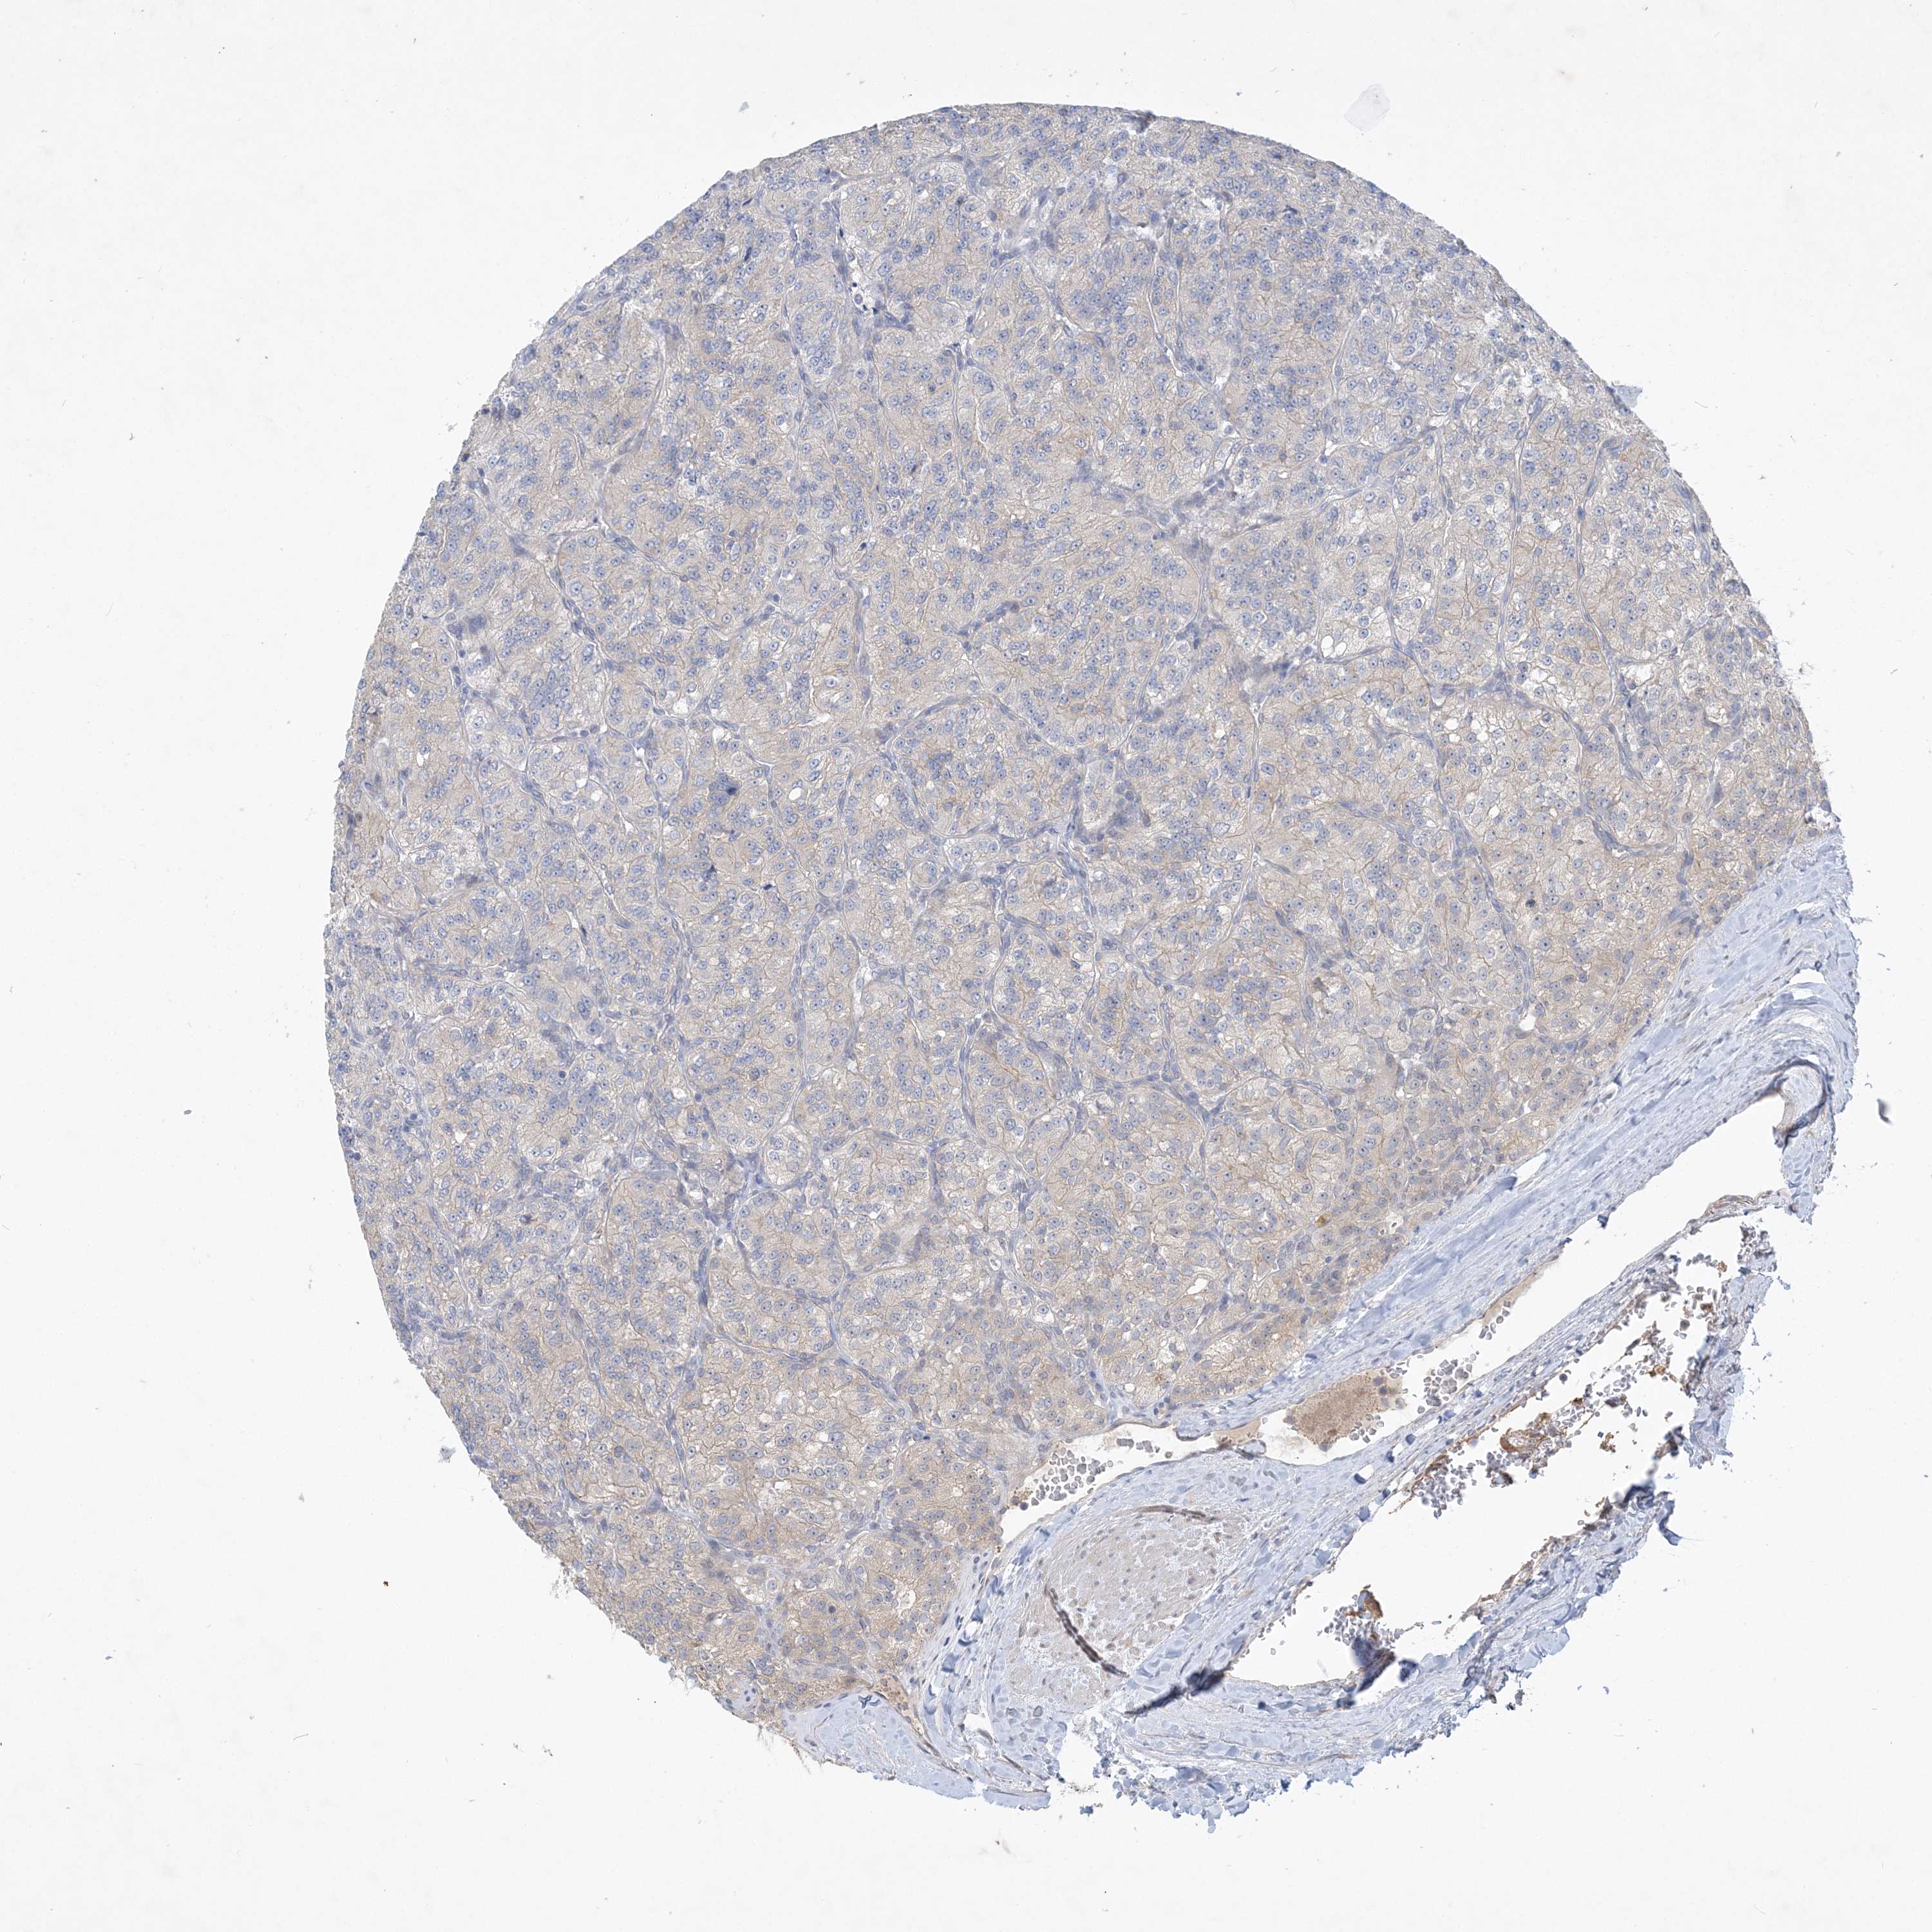

The Survival Scatter plot shows the clinical status (i.e. dead or alive) for all individuals in the patient cohort, based on the same data that underlies the corresponding Kaplan-Meier plots. Patients that are alive at last time for follow-up are shown in blue and patients who have died during the study are shown in red.

& Survival analysisi

Kaplan-Meier plots summarize results from analysis of correlation between mRNA expression level and patient survival. Patients were divided based on level of expression into one of the two groups "low" (under cut off) or "high" (over cut off). X-axis shows time for survival (years) and y-axis shows the probability of survival, where 1.0 corresponds to 100 percent.

ANKRD35 is not prognostic in Kidney Renal Clear Cell Carcinoma (validation)

TCGA RNA samplesi

RNA-seq data is reported as average FPKM (number Fragments Per Kilobase of exon per Million reads), generated by the The Cancer Genome Atlas (TCGA) .

Normal distribution across the dataset is visualized with box plots, shown as median and 25th and 75th percentiles. Points are displayed as outliers if they are above or below 1.5 times the interquartile range. FPKM values of the individual samples are presented next to the box plot.

Average pTPM 0.2

Number of samples 100